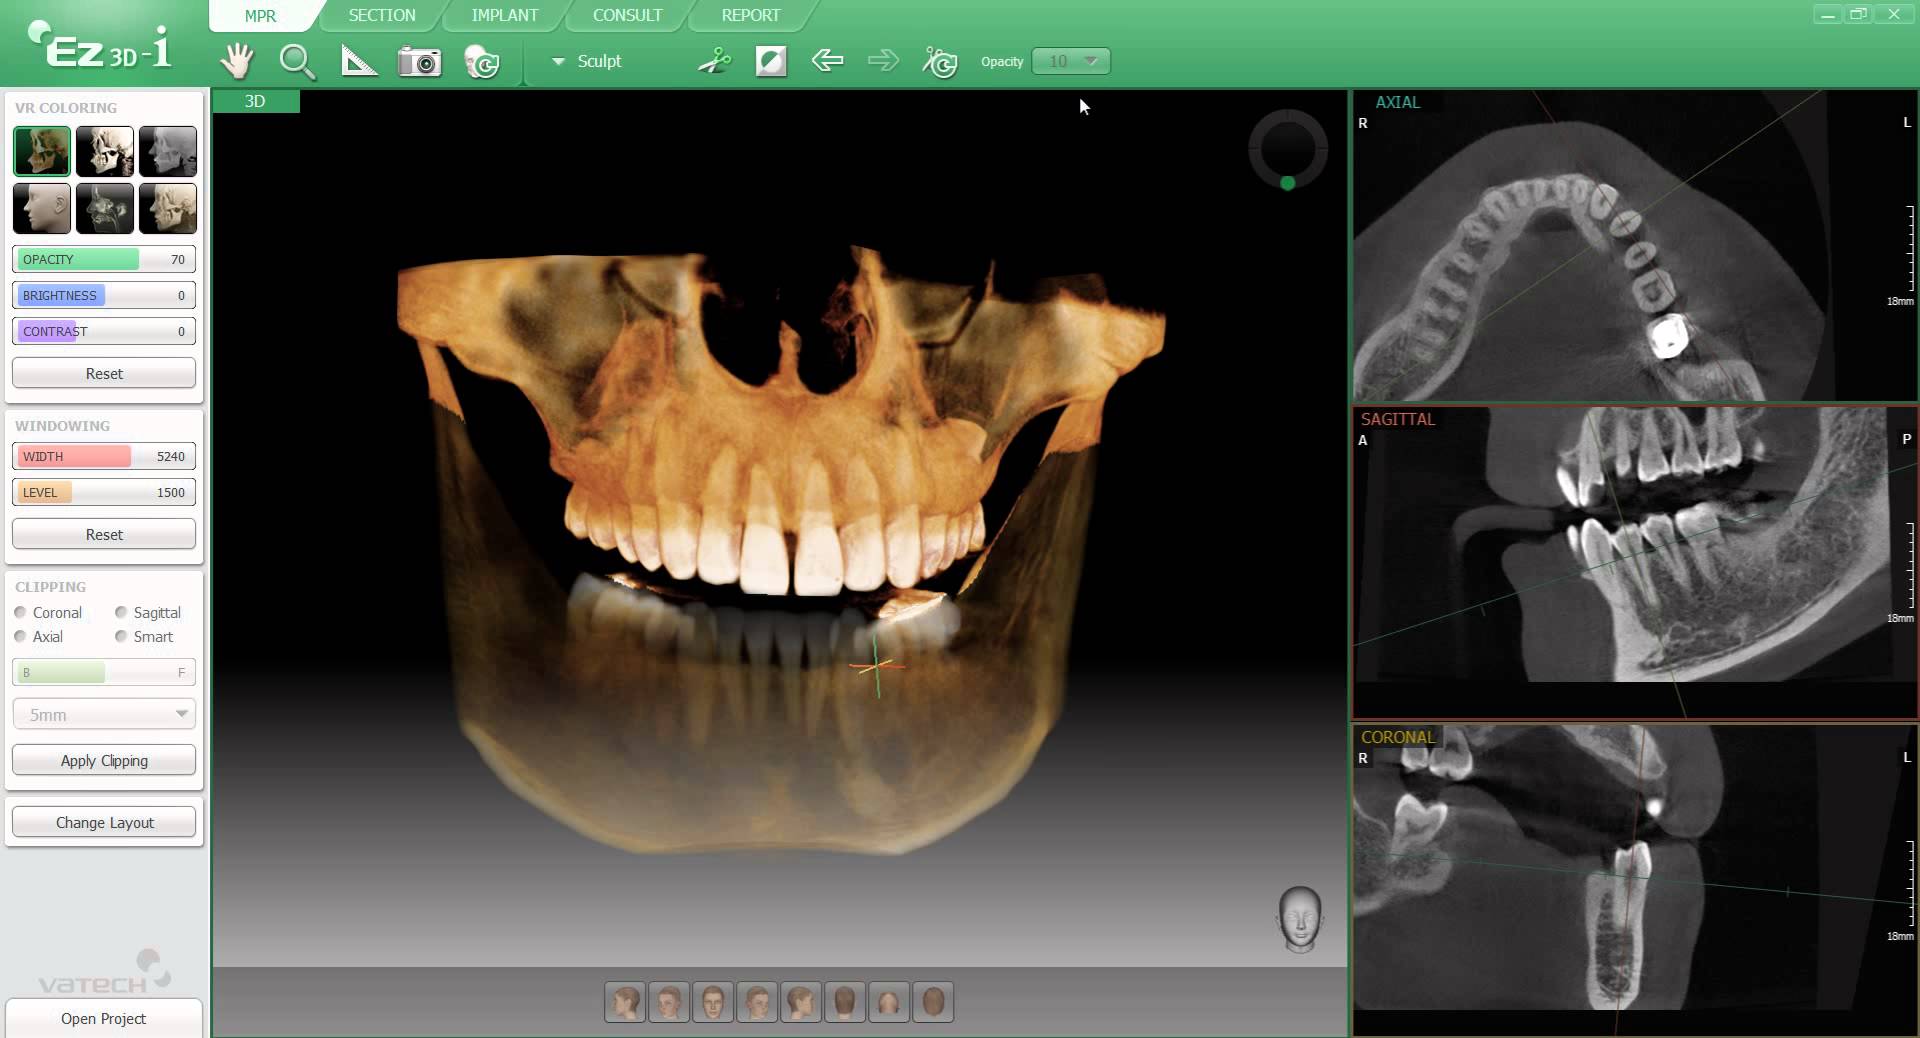

Hoy os hablamos de una exclusiva incorporación tecnológica: un TAC digital 3D de máxima precisión Vatech PaX-i3D

Esta nueva inversión tecnológica, de la que muy pocas clínicas dentales disponen, nos permite realizar un escáner 3D en pocos minutos sin necesidad de desplazarse a un centro radiológico especializado.

Los aparatos disponibles en Centro Dental Pinatar emiten la mínima radiación que permite la tecnología en estos momentos para que no afecten al paciente. Se trata de escáneres extratraorales que muestran imágenes en 3D de la boca del paciente para localizar el punto exacto del problema. De esta forma, médico y paciente se ven beneficiados gracias a la tecnología de última generación que no tienen todas las clínicas dentales.

El escáner ó TAC dental, nos muestra a tamaño real la cantidad y calidad del hueso del maxilar y la mandíbula. Mediante esta prueba podemos medir la altura, la anchura y la densidad del hueso en el que se van a colocar los implantes, todo ello permite al odontólogo identificar con claridad las estructuras anatómicas y planificar la ubicación del implante dental.

Permite diagnosticar anomalías óseas como quistes, tumores, etc… y relacionadas con los senos maxilares como sinusitis, mucoceles, etc…

Esta herramienta se utiliza, prioritariamente, para tratamientos que requieren una imagen lo más precisa posible de la anatomía de la boca del paciente, como en el caso de los implantes, cirugías ortognáticas o extracciones dentales complejas.